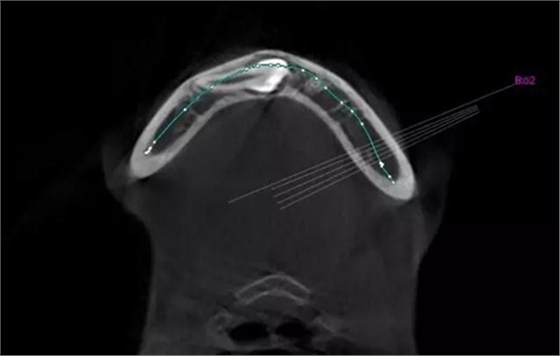

本案:患兒,女,14歲,因牙齒矯正來(lái)院,檢查見(jiàn)83滯留,43未見(jiàn)萌出,拍片發(fā)現(xiàn):43埋伏阻生于31、41、42根尖下方,按照正畸診療計(jì)劃,擬行43拔除術(shù)。

CBCT顯示